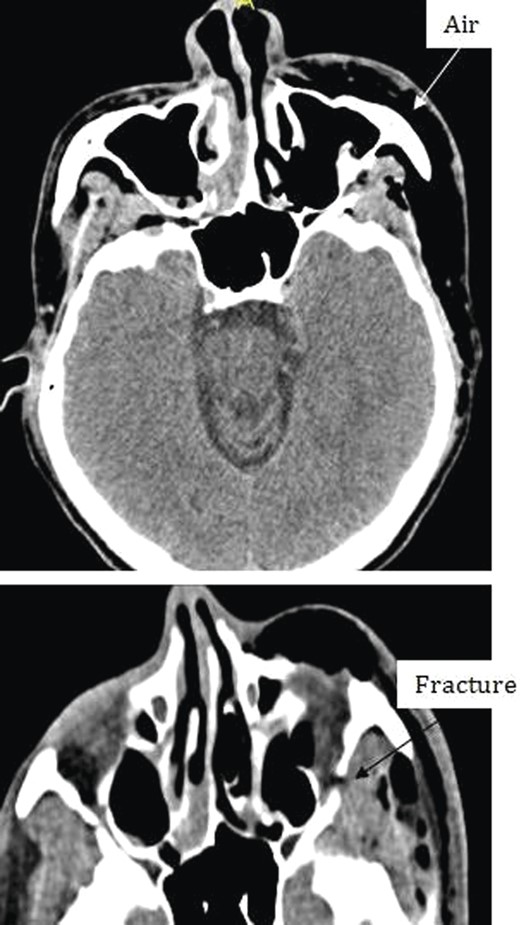

Chest X-ray and head, neck and chest computed tomography (CT) confirmed the diagnosis and extension of PM (Figs 1–3). CT revealed fracture of the floor of left orbit with soft tissue, fat herniation into left maxillary sinus roof, left orbital emphysema with no muscular entrapment. Gas was observed in periorbital tissues, left temporal scalp, infratemporal fossa, left parapharyngeal space and left cheek. Moreover, tissue planes in the neck revealed the presence of air particularly around the carotid vessels, in the posterior triangle and superior mediastinum (PM) around the thymus, trachea (middle), left side of the aorta and anterior to the sternum. However, on auscultation, lungs were clear with and the laryngeal passages and trachea looked normal.

Different levels of head imagining showing fracture of the floor of the orbit and subcutaneous air.